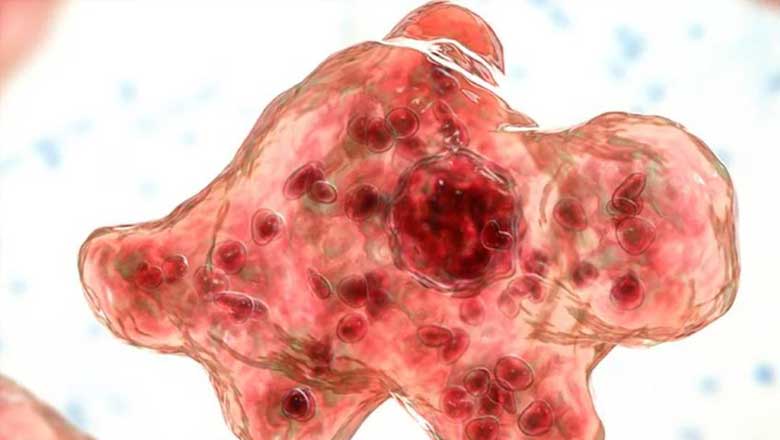

കോഴിക്കോട്: സംസ്ഥാനത്ത് വീണ്ടും അമീബിക് മസ്തിഷ്ക ജ്വരം. കോഴിക്കോട് സ്വദേശിയായ 12 വയസുകാരനാണ് രോഗം സ്ഥിരീകരിച്ചത്. കുട്ടി കോഴിക്കോട്ടെ സ്വകാര്യ ആശുപത്രിയിൽ ചികിത്സയിൽ തുടരുകയാണ്.

കഴിഞ്ഞ ദിവസം കണ്ണൂരിൽ അമീബിക് മസ്തിഷ്ക ജ്വരം ബാധിച്ച് 13 വയസുകാരി മരിച്ചിരുന്നു. കണ്ണൂർ സ്വദേശി രാഗേഷ് ബാബു-ധന്യ ദന്പതികളുടെ മകൾ ദക്ഷിണയാണ് മരിച്ചത്.

ദക്ഷിണ കോഴിക്കോട് ബേബി മെമ്മോറിയൽ ആശുപത്രിയിൽ ചികിത്സയിലായിരുന്നു. ഈ മാസം 12നാണ് കുട്ടിയെ ആശുപത്രിയിൽ പ്രവേശിപ്പിച്ചത്.